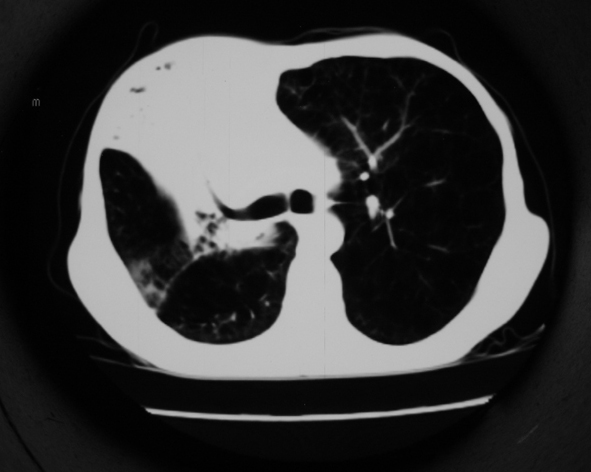

男53岁,咳嗽气短,以往身体健康.

右肺上叶多发多形态空洞及增殖灶,可见团块钙化,胸膜肥厚、粘连,考虑继发型肺结核可能性大

1.右肺上叶干酪性肺炎,2。肺气肿,肺大泡

右肺上中叶结核干酪性肺炎

右肺中上叶干酪性肺炎。

支持右上肺继发性肺结核并干酪性肺炎,右肺大泡,左肺代偿性气肿。